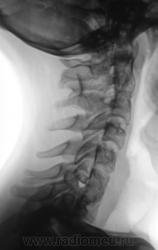

Сколиоз-то сколиоз, но генеза "аномального".

Это синостоз тел верхних шейных позвонков и С6-С7? И боковые клиновидные полупозвонки в верхнегрудном отделе? Это синдром Клиппеля-Файля? А может и Шпренгеля...

Поражает, что только сейчас выявлена такая выраженная дисплазия..там видимо и по органам проблемм хватает..